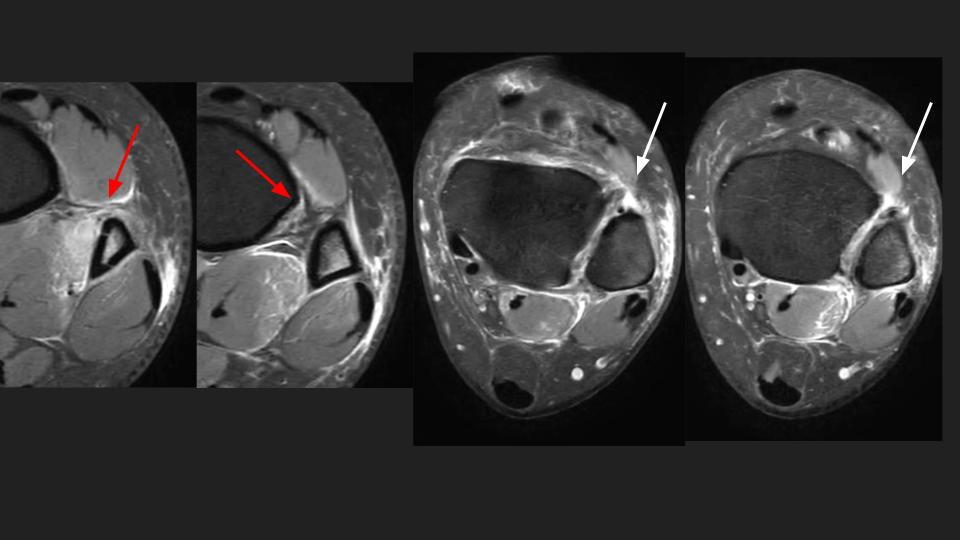

There is non displaced distal fibular shaft fx (see XR). There is a partial tear of the interosseous membrane (red arrows). There is complete AITFL rupture (white arrows). Gr I sprain of the PITFL and Laciniate ligaments. I think there is double band morphology of the ATFL, with a complete tear of one band and the other band intact (blue arrow). There is partial tear of the CFL (yellow arrow)...generally the CFL tears after the ATFL. The key point is that there should ALWAYS be overlap of the distal tibial and fibula in the Oblique or Mortise view...in this Obl view there is none. Syndesmotic Complex injury should have been suspected on the basis of the XR findings.